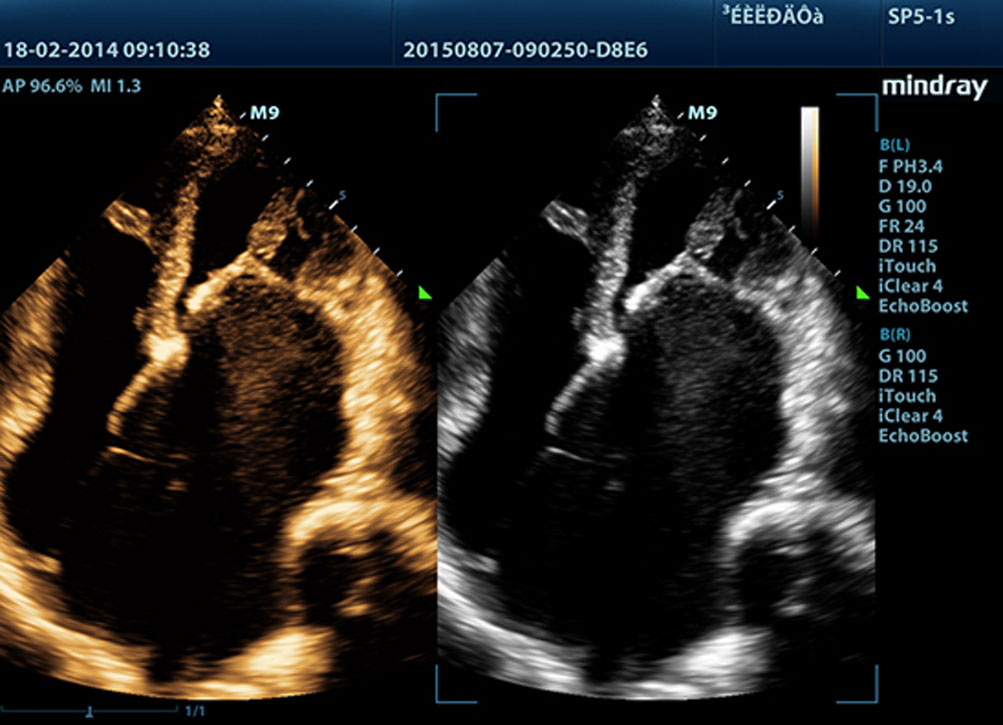

Sulla base della piattaforma ecografica di nuova generazione Mindray, mQuadro, M9 ha alzato gli standard di settore ad un livello tutto nuovo. Processori avanzati di trasmissione e ricezione del segnale forniscono un rilevamento dell'eco altamente sensibile e preciso. Le tecnologie innovative dei trasduttori consentono una migliore penetrazione, una risoluzione pi├╣ alta, migliorando notevolmente lŌĆÖesperienza diagnostica.

Fornendo immagini pi├╣ nitide, tutte le sonde compatibili con M9 sono dotate della tecnologia Mindray tecnologia trasduttore 3T, unica nel suo genere. Migliorato con l'aggiunta della tecnologia monocristallo, M9 offre una migliore penetrazione e un flusso dinamico del colore, in particolare durante la scansione di pazienti difficili.

La tecnologia Mindray di elaborazione adattativa del segnale con rilevamento dell'eco intelligente, unica nel suo genere, progettata per utilizzare le informazioni native segnale-rumore per migliorare i segnali eco deboli, mentre sopprime i disturbi del rumore circostante, fornendo una pi├╣ equilibrata luminosit├Ā dellŌĆÖimmagine ed una migliore visone degli strati di tessuto miocardico.